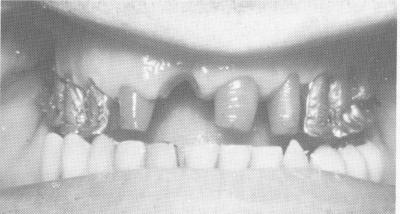

Fig. 15-22. The patient before treatment closed in this position—a Class III relationship.

1 Class III relationship closed position before intervention